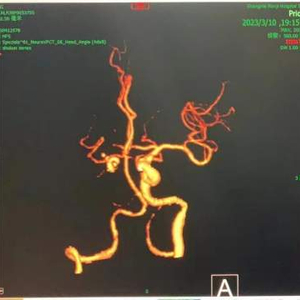

(术前、术后患者的脑部血管CTA成像)

3月10日傍晚,120载着昏迷老人驶入仁济医院,急诊卒中小组已经守候,并启动卒中绿色通道。医生们迅速给患者进行心电图、血检、头颅多模态影像检查。经评估,确认老人为急性右侧颈内动脉栓塞脑梗死,头颅CT灌注提示右侧大脑半球大面积低灌注并存在“缺血半暗带”。